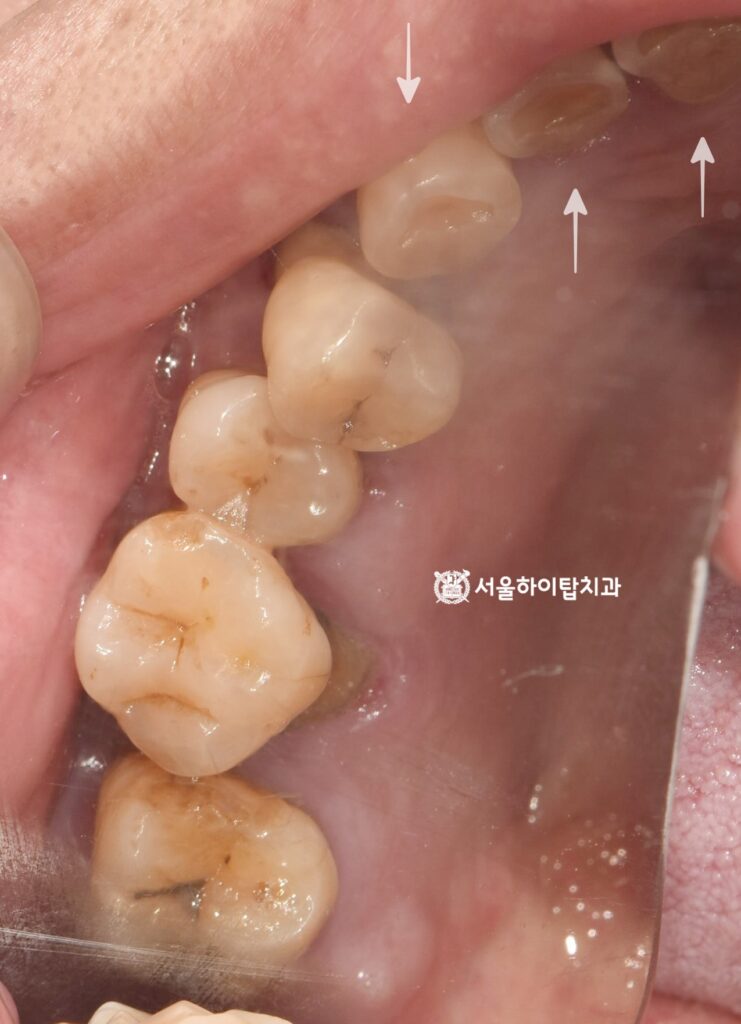

이어서 구강 내 모습을 살펴보면,

주안동 치과 에서는 곳곳에 치태와 플라그가

쌓여 있는 것을 확인할 수 있습니다.

특히 화살표로 표시된 교합면에서는

심한 마모가 관찰되는데,

이는 앞서 상실된 어금니 때문에

전치부(앞니)로 음식을 저작했을

가능성을 시사하는 소견입니다.

이처럼 비정상적인 저작 패턴은

마모를 가속화할 뿐만 아니라,

장기적으로 자연치 구조와

치은 건강에도 영향을 미칠 수 있습니다.